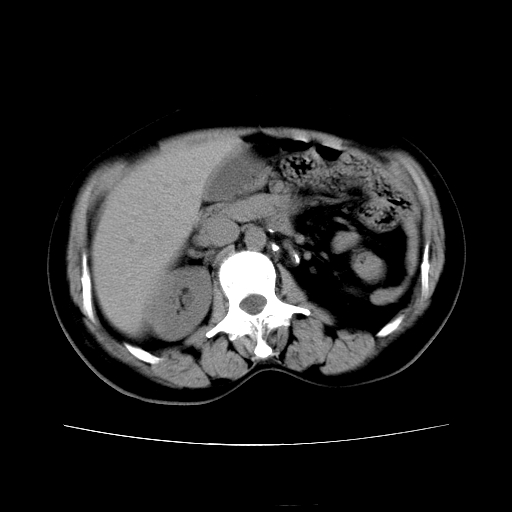

女45y多次(7次)碎石,结果不理想!曾碎石后尿出小碎石,仍腰痛,要求ct,其它不详.本人更倾向于钙化斑!无肾实质破坏,积水等提示集合系统无梗阻.另外腹腔多处钙化.是否结核后改变!谢谢赐教!

1)双肾结石。2)脾脏钙化灶。3)腹膜后多发淋巴结钙化。

尿路结石与腹部淋巴结钙化共存,建议v尿路造影检查,免得钙化灶冤枉为结石受罚。

考虑双肾结石,肾脏实质无破坏表现,没有结核病史,不考虑肾结核,